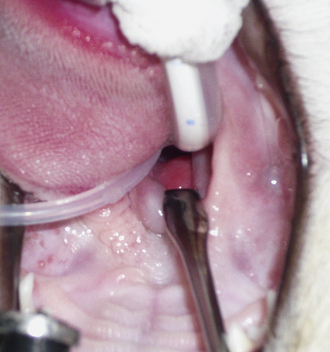

The hallmark symptom of nasopharyngeal disease is stertor. Discharge, sneezing, reverse sneezing, and hacking may be present variably. If the main complaint is noisy breathing and not productive sneezing with nasal discharge, the nasopharynx may be the site of primary disease. The most common primary problems in the nasopharynx in cats are inflammatory polyps and tumors.12,13 Cats with polyps are generally young and have a history of noisy breathing. Sneezing and mucopurulent nasal discharge may be present, but the chief complaint is stertor and increased respiratory effort. This is a problem that often requires otoscopic as well as rhinoscopic intervention. With the patient placed in dorsal recumbency, the soft palate is reflected rostrally with the use of a spay hook, and the polyp is removed via traction and avulsion (Figures 19-18 and 19-19). The eustachian tube orifices can generally be directly visualized and any remaining tissue removed, if present. Both ears should be carefully examined, and transtympanic bulla curettage should be performed to remove any middle ear proliferative tissue (see Chapter 20). In older cats with similar symptoms, a neoplasm in the nasopharynx is more likely, and rhinoscopy is often much more rewarding (Figure 19-20). Foreign bodies can become lodged in this area after vomiting or pharyngeal nasopharyngeal spasms induced by attempted swallowing of the foreign object. Nasal and nasopharyngeal stenosis after trauma, nasogastric reflux,14 and chronic rhinitis can occur in dogs and cats (Figures 19-21 through 19-23). Reflux can occur during general anesthesia and can be a helpful clue if postoperative symptoms arise and persist. Congenital choanal atresia and nasopharyngeal dysgenesis have also been reported in dogs.15,16 Nonspecific chronic inflammation of the nasopharynx causes a cobblestone appearance of the mucosa due to the formation of hyperplastic lymphoid follicles (Figures 19-24 and 19-25). Chronic inflammation may be the result of a lymphoplasmacytic rhinitis complex or sometimes may be secondary to otitis media and middle ear drainage of infected secretions via the eustachian tube. Otoscopy is recommended in any patient with nasopharyngitis of unknown origin. CT studies performed in a population of 45 cats with chronic sinonasal discharge revealed effusive bulla disease in 28% of symptomatic cats.17 Unfortunately, we are unable to differentiate primary and secondary pathology based on the concurrence of nasal and middle ear disease. Regardless of the knowledge of the primary cause, both inflammatory foci should be treated to achieve symptom relief.

image

Figure 19-18 Feline nasopharyngeal polyp visualization via soft palate retraction.

Figure 19-19 Feline benign nasopharyngeal polyp extraction.